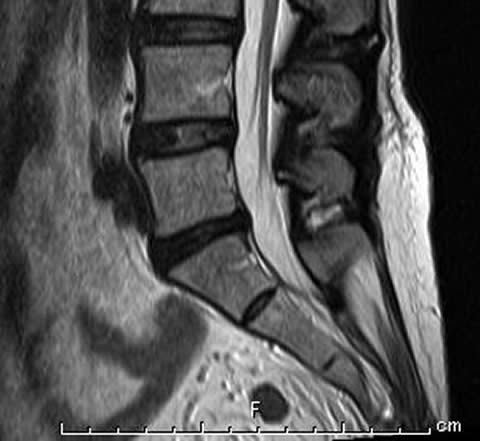

MRIとは核磁気共鳴画像(Magnetic Resonance Imaging)の略です。

MRI検査は、非常に強力な磁石でできた筒状の装置に入り、磁気や電波を利用して人体のさまざまな断面を撮影する検査です。X線撮影やCTのようにX線を使用していないため、放射線被ばくはありません。

当院では1.5テスラ超伝導式装置が導入されています。

検査空間も従来のMRI装置よりも広くなり、より開放感のある検査環境となっているため、閉所恐怖症の患者様や体格の大きな患者様もより快適に検査を受けられます。

また、静音性の技術が搭載されているので、騒音の少ない検査を受けられます。

腰椎